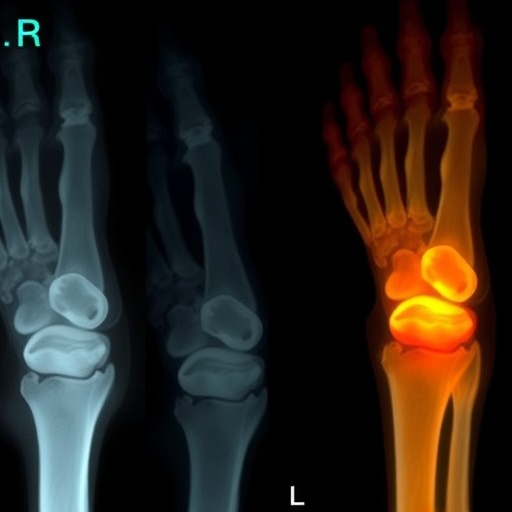

In a striking case report published in BMC Pediatrics, researchers Zhao, Dai, and Wang present an intriguing instance of neonatal Candida osteomyelitis with accompanying septic arthritis. This rare and severe condition presents significant challenges in medical management, particularly because it involves an infection caused by Candida, a type of yeast that typically does not cause harm in healthy individuals. The details unravelled in this study provide critical insights into the implications of fungal infections in neonates, a population that is particularly vulnerable to severe infections due to their immature immune systems.

The incidence of ostemyelitis and septic arthritis in newborns is extraordinarily low, making this case not only remarkable but also vital for understanding the risks associated with Candida species. Neonates, due to their limited immune defenses, can experience life-threatening situations from infections that are often considered benign in older children and adults. Hence, when such infections arise, they present a medical conundrum that requires prompt recognition, diagnosis, and management to improve outcomes.